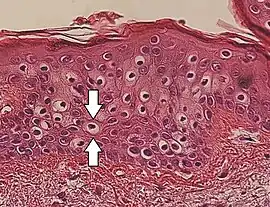

Perinuclear vacuolization of epidermal keratinocytes (one indicated by arrows), in this case an insignificant incidental finding.

Vacuolization is the formation of vacuoles or vacuole-like structures, within or adjacent to cells. Perinuclear vacuolization of epidermal keratinocytes is most likely inconsequential when not observed in combination with other pathologic findings. In dermatopathology "vacuolization" often refers specifically to vacuoles in the basal cell-basement membrane zone area, where it is an unspecific sign of disease.[1] It may be a sign of for example vacuolar interface dermatitis, which in turn has many causes.